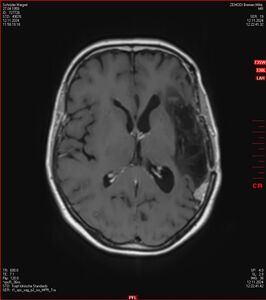

Die letzten drei Bilder Zeigen aus meiner Sicht den Tumor, der im Jahr 2021 bestrahlt wurde.

Zum Vergleich nun auch die Bilder vom 1.12.2023:

Ich denke, in den letzen 12 Monaten sind da ein paar Rezidive gewachsen,  vor 12 Monaten waren sie auch schon zu erkennen - vorher noch nicht. Nun hoffe ich auf den Rat des Spezialisten. Hoffendlich kann man etwas machen.